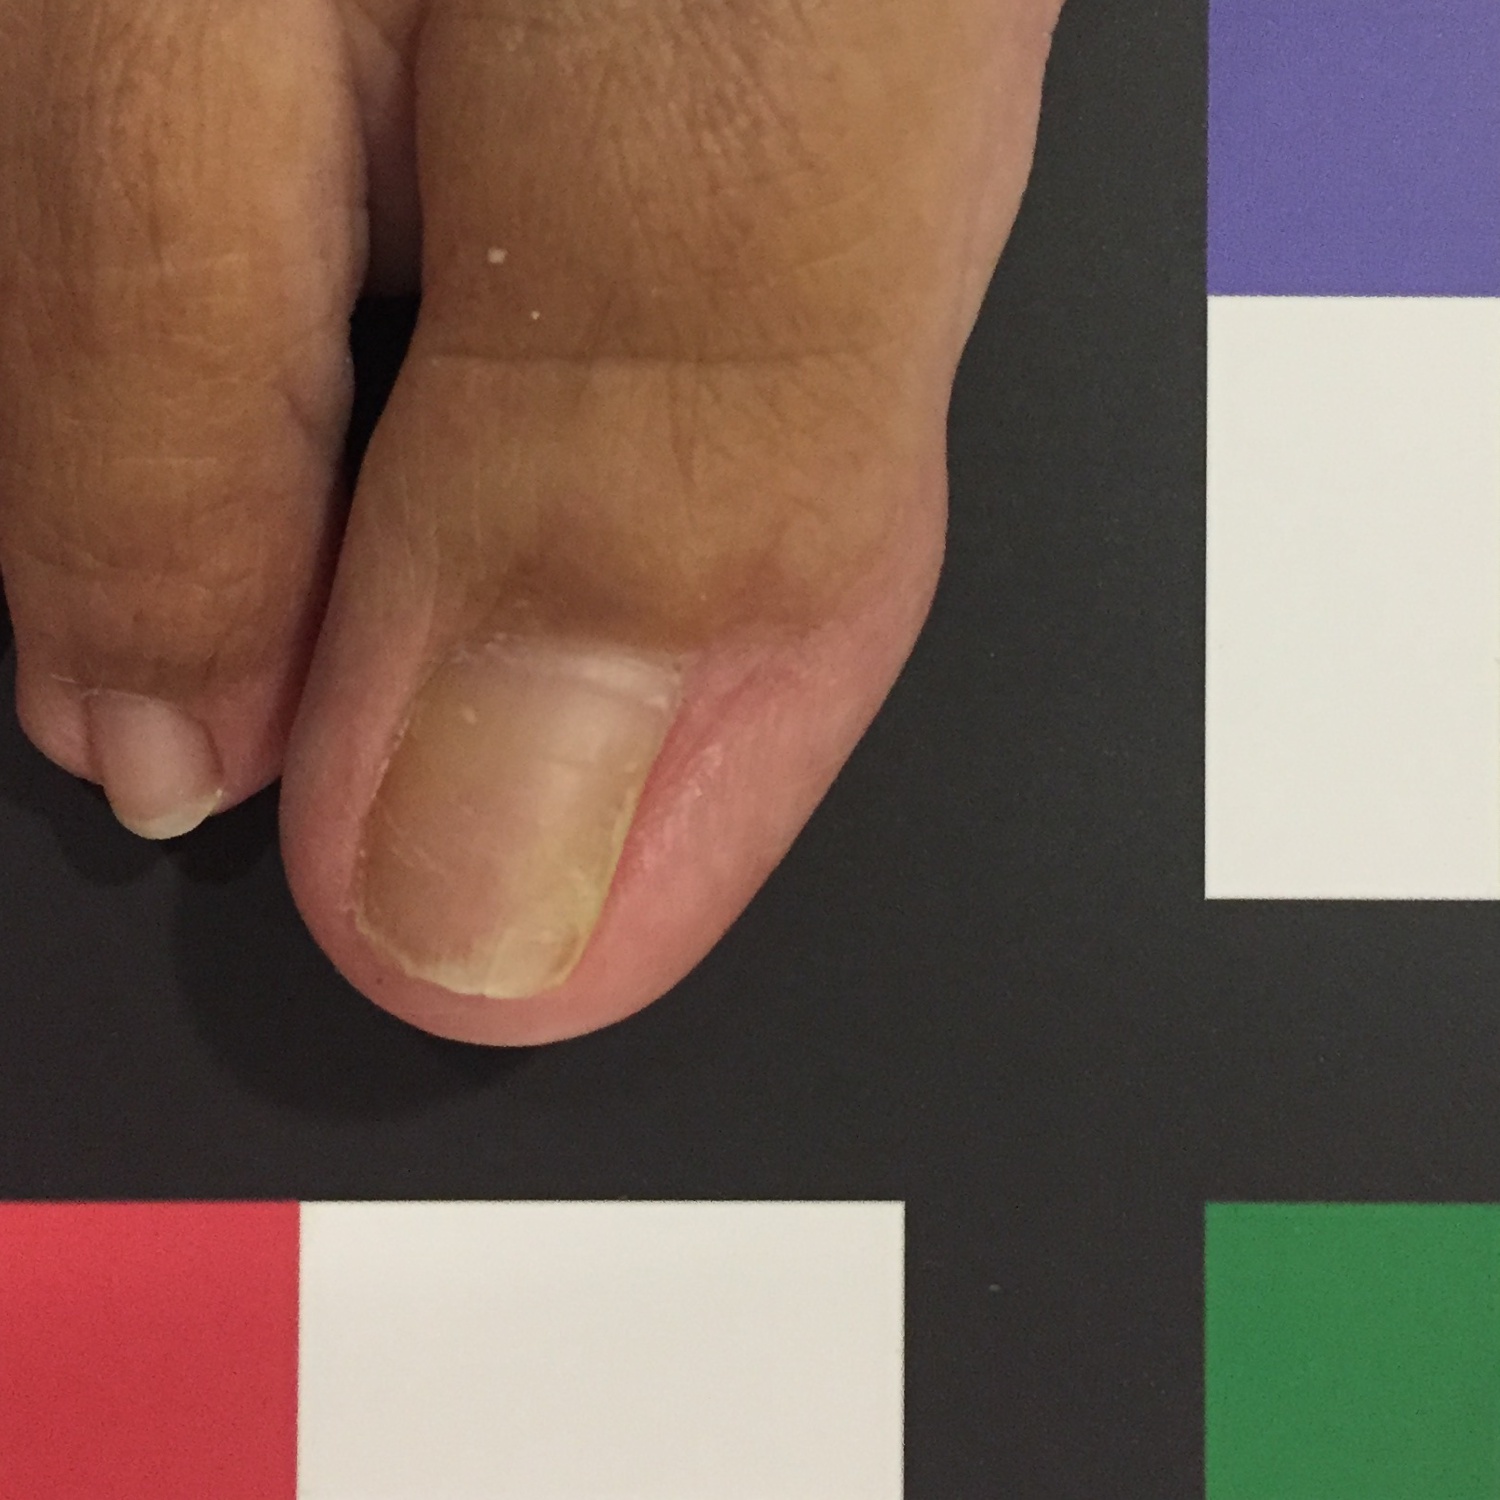

The dataset used in this study was taken in the clinical practice. Following the guidelines of a well-defined medical study, images were acquired in real conditions. All of them were captured in the doctor’s office with their smartphones’ embedded camera. To control some of the environmental conditions, we designed a template to use as the scene background (see Figure 2). During the acquisition process, however, we could not control some other environmental conditions, such as the capture viewpoint the camera setup or the illumination.

The dataset is composed of 348 images of human big toes acquired using the doctor’s cameras attached to off-the-shelf smartphones. A sample image is found in Fig. 8. As previously explained, during the image acquisition stage, some parameters could not be controlled, such as the illumination, the specific capture viewpoint and the camera specifications.